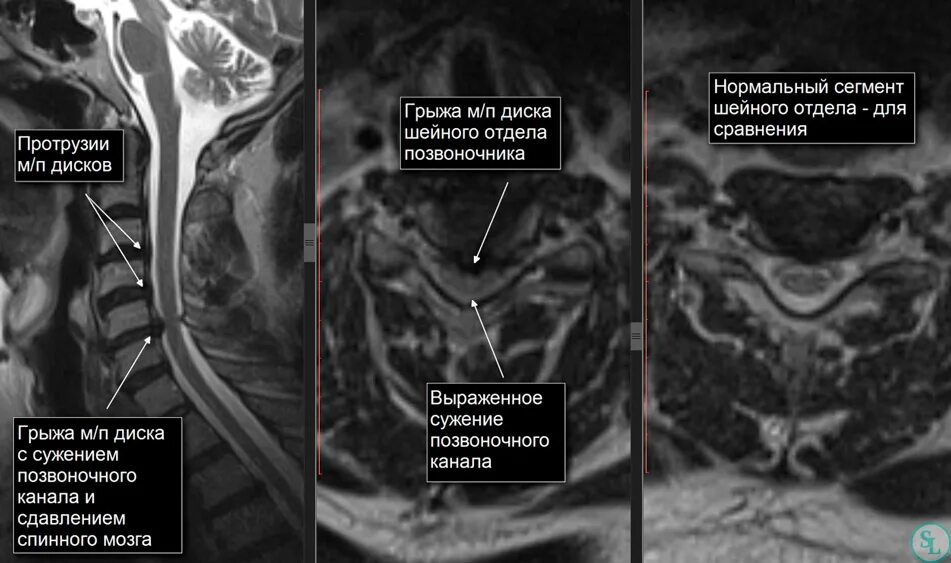

Как лечить стеноз шеи